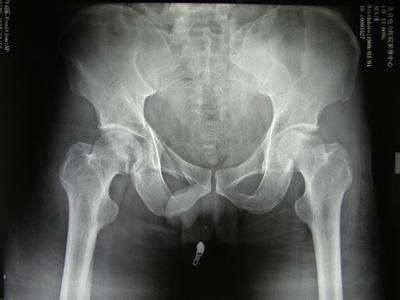

ˋ▽ˊ 不稳定型骨盆骨折治疗进展及注意事项揭秘具体方案的制定有助于开放或闭合性骨盆骨折的规范处理。待骨盆骨折患者病情趋于稳定后可行手术治疗,达到解剖复位并恢复功能便成为最终目标。 目前,对于不稳定型骨盆骨折,其诊治缺乏规范、系统的流程。 近年来,国内外骨科医师珍对骨盆骨折的诊断及治疗进行了多方面研究,本文...

女子遭重石砸伤危在旦夕,烟台山医院多学科协作成功救治齐鲁晚报·齐鲁壹点 孙淑玉 通讯员 张国杰 曲高伟近日,烟台的李女士突遭横祸,被重约两吨的石块砸伤骨盆,危在旦夕。考虑到患者病情危重,烟台山医院迅速为其开通绿色通道,多学科联动为其成功保命。病情凶险,李女士被送到医院时,已经不省人事。在完成补液、输血,生命体征平稳后...